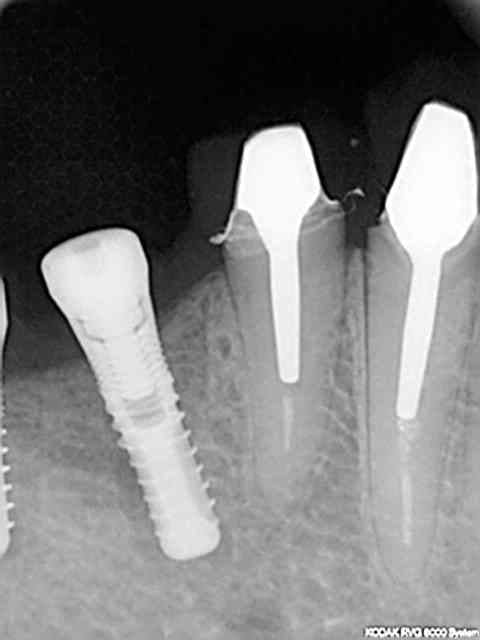

la rvg en question

Image o 3 av8pra - Eugenol

A mon avis cette reconstruction osseuse est à mettre en rapport avec plusieurs éléments :

1) technique en un temps si il avait fallu faire un lambeau jamais cela ne se serait produit

2)pas de curetage

3)mise en fonction malgrè tout donc stimulation osseuse

4)maintenance douce par le patient (qui nous a quand même oublié trois ans...)

5)j'ai changé de capteur radio entre temps avec une définition sans comparaison et je pense que malgré tout avec un capteur précis les premières rvg de 2001-2002 auraient montré un semblant de trame osseuse .quant aux doutes sur la chronologie regardez la marque des capteurs et vous verrez que l'on n'utilise pas une rolls dans un premier temps puis un solex après...

suite à ce cas que j'avais posté

hier fait une rvg de controle sur deux implants posés en 2007 (serf evl+) et en mésial on distingue nettement que l'os s'est formé sur le col lisse...

explications ?